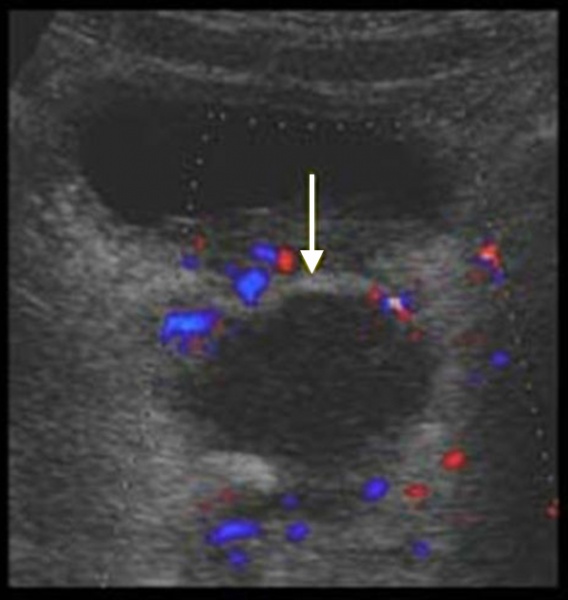

10 Диагностика При УЗ-исследовании межкишечные абсцессы лоцируются в виде аперистальтичных образований неправильной формы. Иногда возможно проследить тонкую гиперэхогенную капсулу, но чаще контур остается нечетким, неровным. Содержимое сниженной эхогенности и никогда не бывает анэхогенным, структура неоднородна.

Для дифференциальной диагностики с тубоовариальным абсцессом у женщин проводится УЗИ малого таза; для исключения абсцесса предстательной железы у мужчин – УЗИ простаты.

В сложно дифференцируемых случаях может потребоваться выполнение компьютерной томографии, МРТ. Для окончательного распознавания абсцесса дугласова пространства прибегают к диагностической пункции гнойника под ультразвуковым наведением через прямую кишку либо задний свод влагалища. Полученное гнойное содержимое подвергается бактериологическому исследованию.